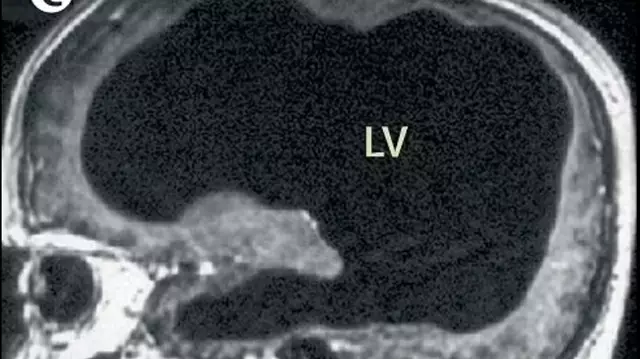

A 44-year-old man in France stunned the medical world when he went to the doctor for a leg ache. After a routine scan, doctors discovered that most of his brain was missing. Instead of brain tissue, his skull was mostly filled with fluid.

The man had a condition called hydrocephalus, often known as “water on the brain.” He was diagnosed as an infant and treated with a tube to drain the fluid. However, the tube was removed when he was 14. Over the next 30 years, the fluid slowly built up and pushed his brain tissue against the walls of his skull.

Despite having very little brain tissue left, the man lived a perfectly normal life. He was married, had a family, and held a steady job. While his IQ was slightly below average, he showed no signs of significant mental impairment.